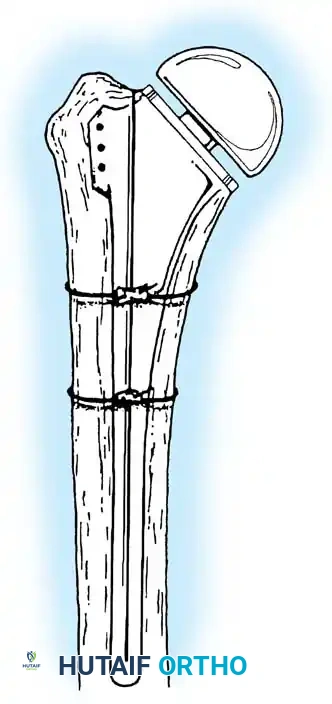

3. Canal Preparation and Implantation

The humeral and ulnar canals are sequentially broached.

- A cement restrictor is placed in both canals.

- Antibiotic-loaded polymethylmethacrylate (PMMA) bone cement is injected in a retrograde fashion.

- The components are inserted, and the articulation is linked using the manufacturer-specific locking pin mechanism.

- Periprosthetic Fracture: Particularly common at the tip of the humeral or ulnar stems due to stress shielding and osteoporotic bone.